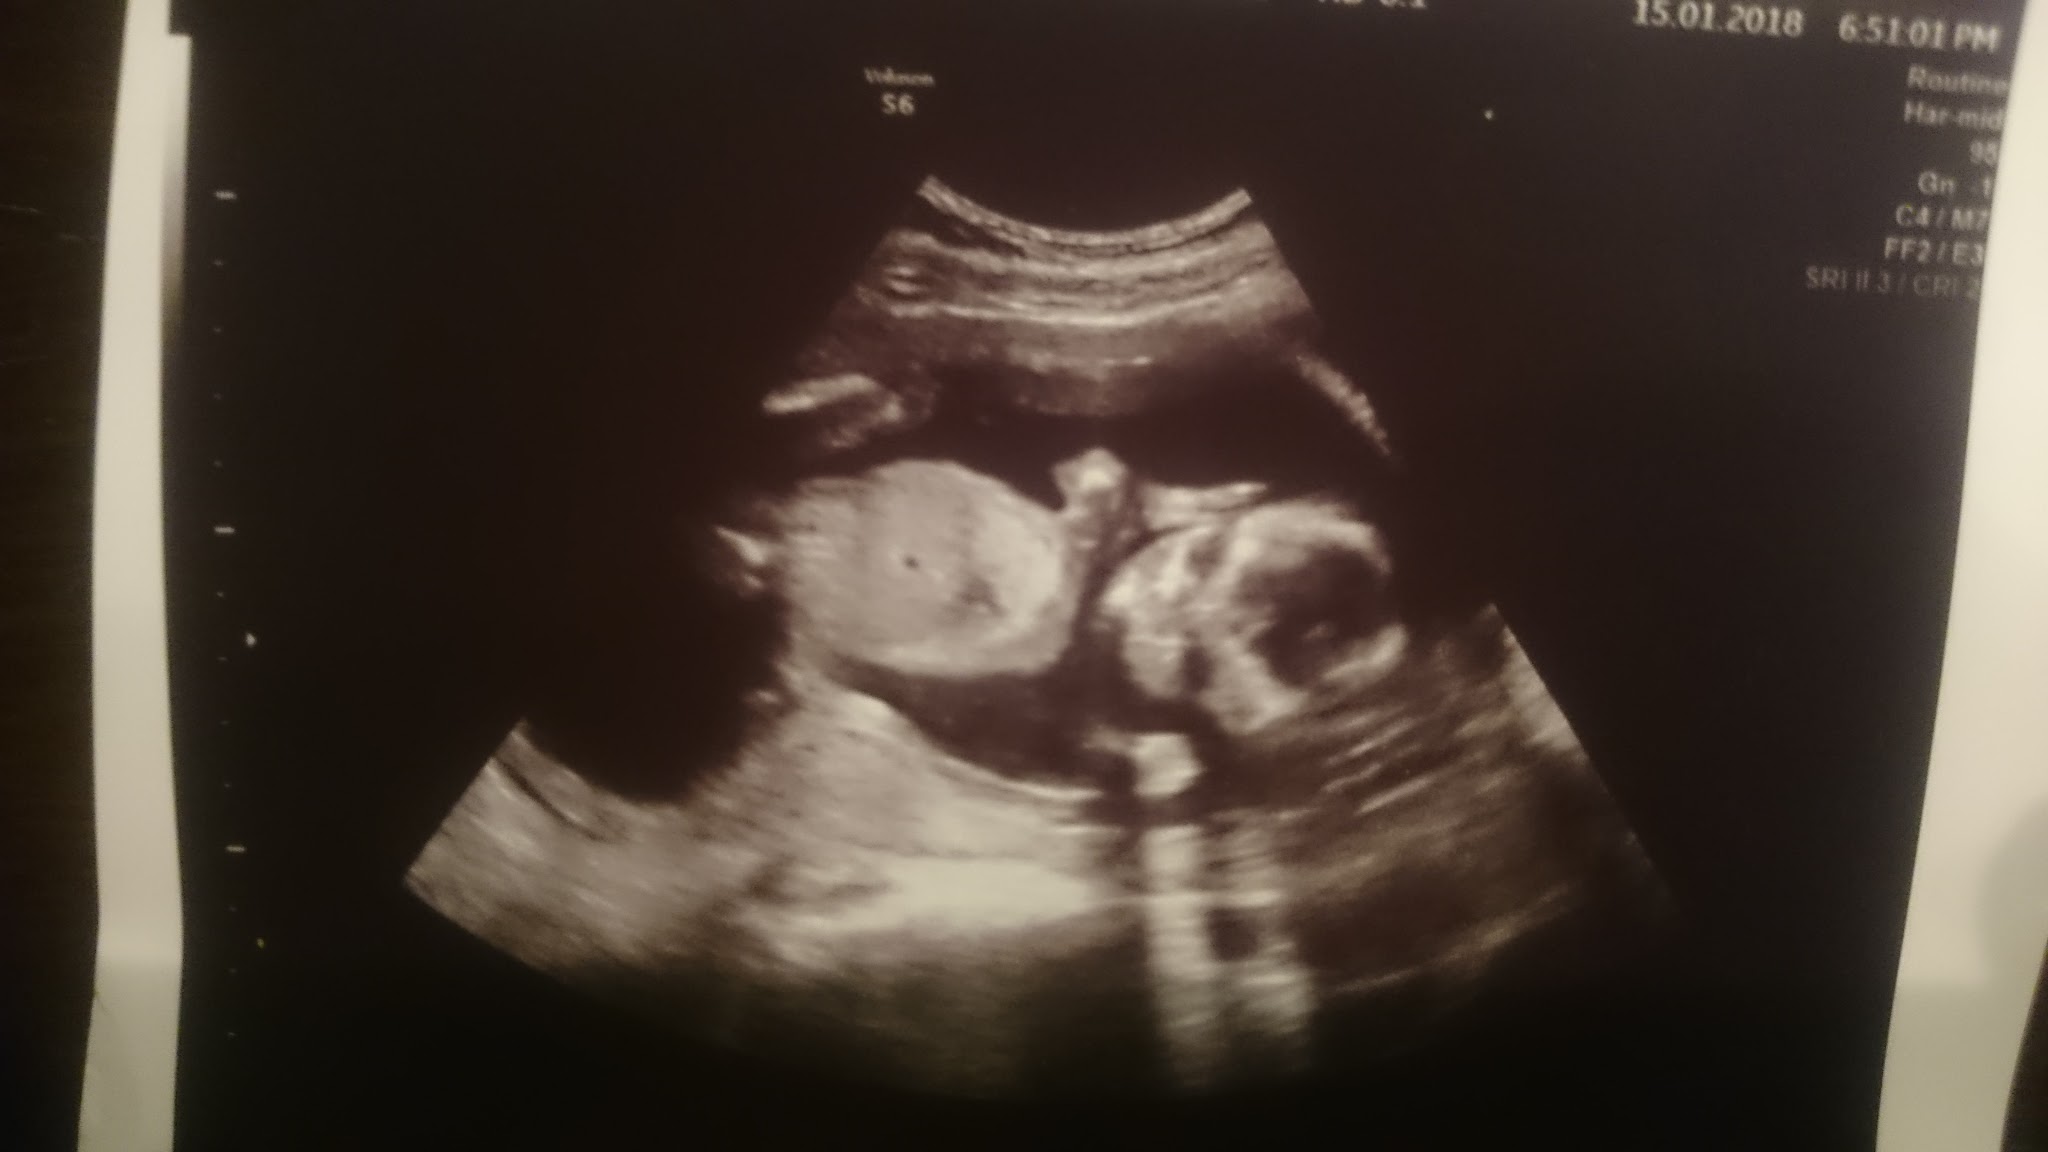

Slicznosci[emoji3]U mnie też ostatnio jakoś depresyjnie. Trochę słońca by się przydało. Ale USG zawsze poprawia nastrójOto moje szkraby. Jeden niestety się chowa.

Zobacz załącznik 836008 Zobacz załącznik 836007